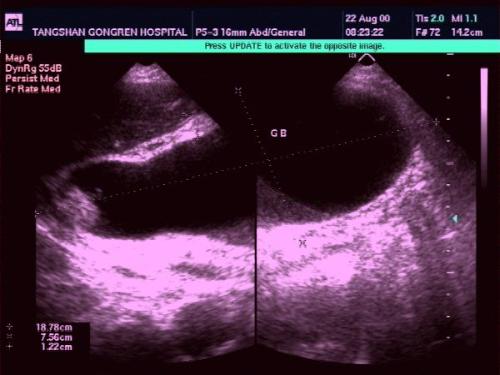

后来的一次发作,刘大妈被子女送到县医院,在那里做B超发现是“胆结石”,手术后康复。